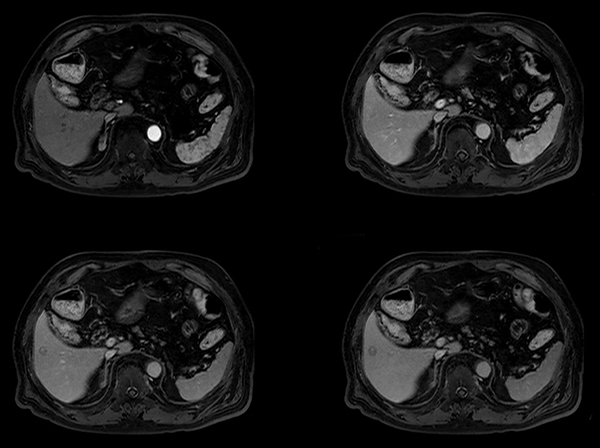

Dynamic eTHRIVE